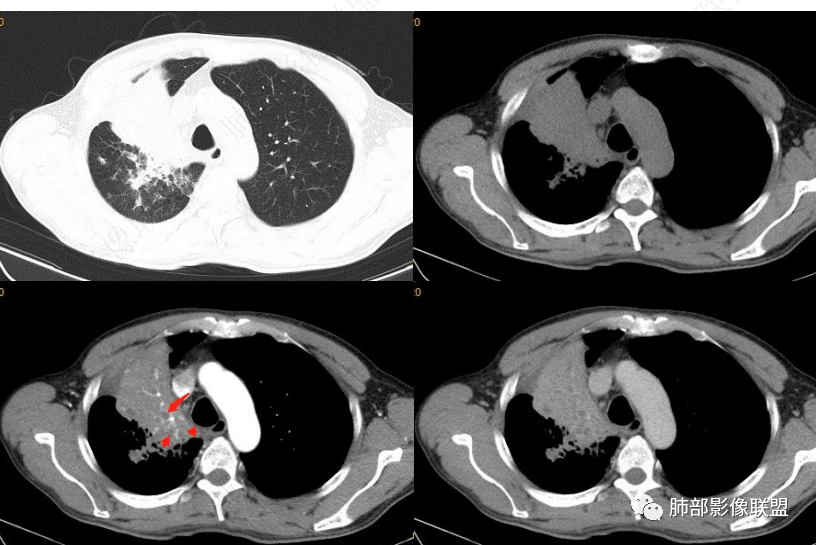

就是看不清下面的支气管壁

一般如果炎症,支气管壁会延续过来,

远端粘液栓

一般来说炎性的是近端支气管狭窄,腔内粘液栓

这个支气管壁没显示出来

就怕腔内占位堵塞不全

下图是炎性的

一般支气管狭窄一些,壁弥漫增厚

这是炎性特点,壁弥漫增厚,腔内粘液栓

这例也是,只是我调节不理想,壁其实也是弥漫增厚,腔狭窄,腔内粘液栓

这是炎性的,支气管壁弥漫增厚,近端腔狭窄